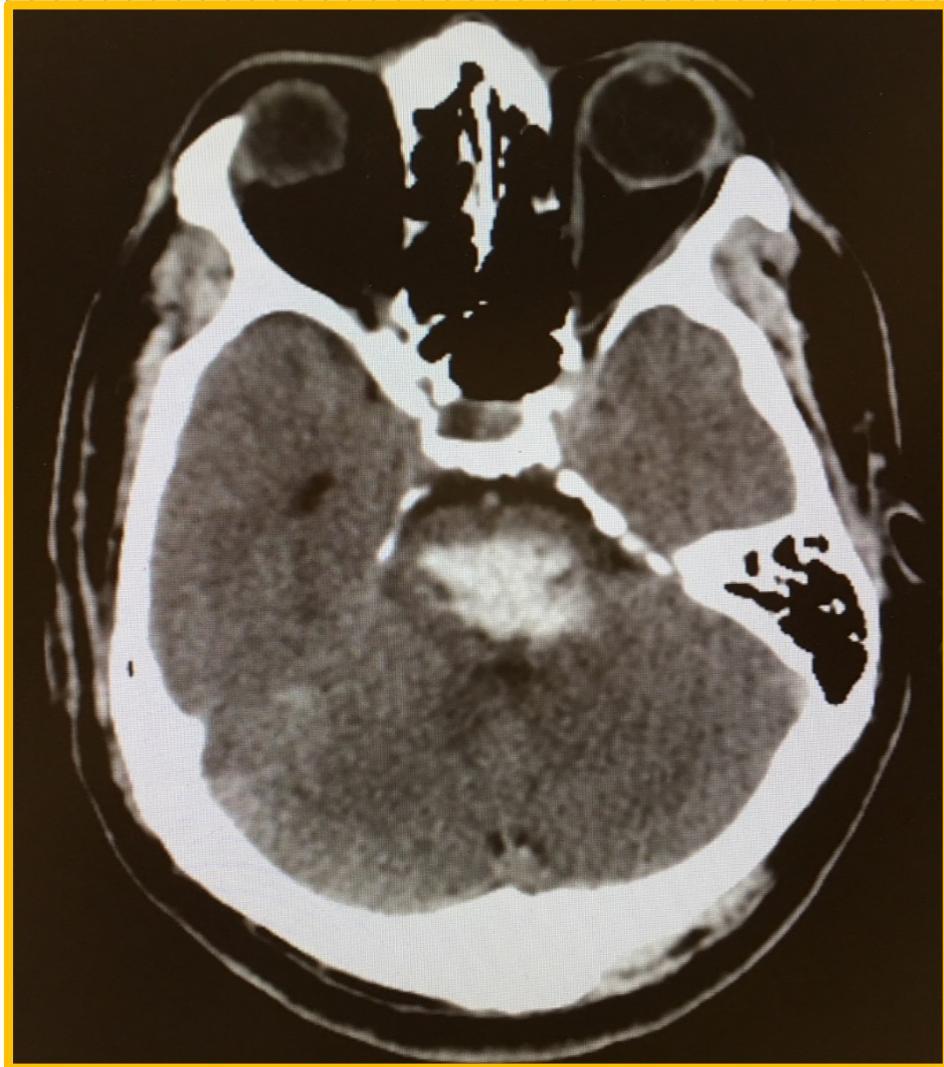

âLocked-Inâ Syndromeâ

Locked-in syndrome (LIS) is a complex medical condition presenting with quadriplegia, bulbar palsy, and whole-body sensory loss due to damage in the brain stem, commonly the anterior pons.

Cognition, vertical eye movement, blinking, and hearing are classically preserved in patients suffering from the condition.

A large pontine hematoma